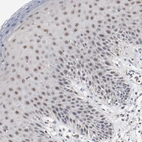

Immunohistochemical staining of human skin shows moderate nuclear positivity in squamous epithelial cells.